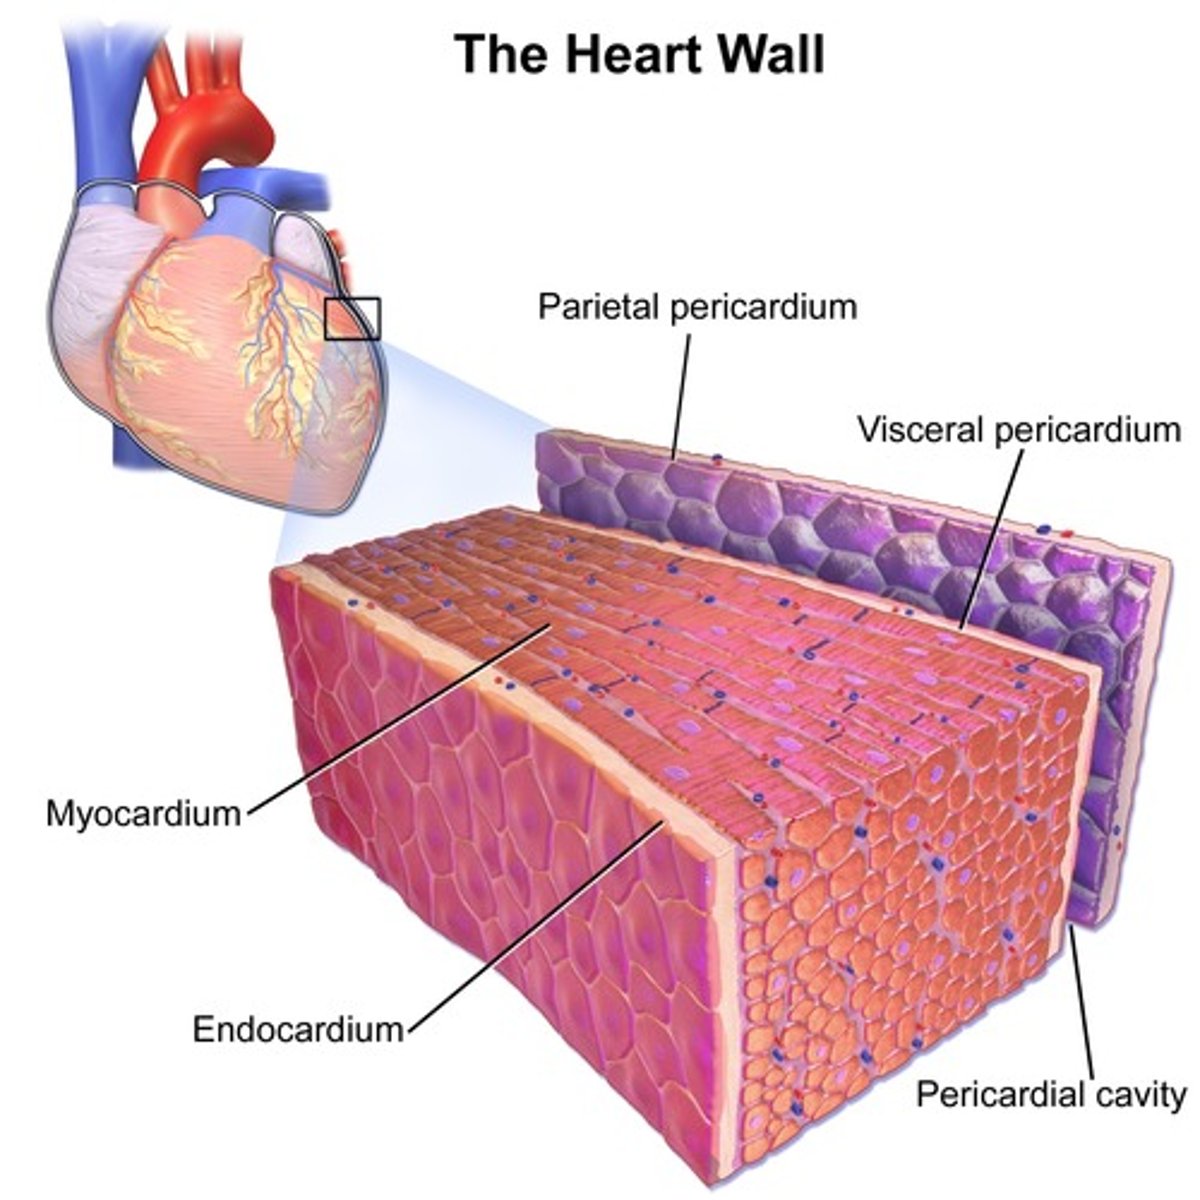

osierdzie

pericardium

Jakie rodzaje osierdzia wyróżniamy?

surowicze i włókniste

osierdzie surowicze

serous pericardium

Z jakich części składa się osierdzie surowicze?

z blaszki trzewnej i ściennej

blaszka trzewna osierdzia surowiczego

visceral layer of serous pericardium

blaszka trzewna osierdzia surowiczego inaczej

nasierdzie

nasierdzie

epicardium

blaszka ścienna osierdzia surowiczego

parietal layer of serous pericardium

Gdzie znajduje się jama osierdzia?

między blaszką ścienną i trzewną osierdzia surowiczego

jama osierdzia

pericardial cavity

Jak jest położone nasierdzie?

ściśle zrośnięte z powierzchnią zewnętrzną serca

Jak odróżnić blaszkę ścienną osierdzia surowiczego i osierdzie włókniste?

Nie da się - są ze sobą zrośnięte

Co znajduje się w jamie osierdzia?

płyn surowiczy umożliwiający ślizganie się blaszek osierdzia